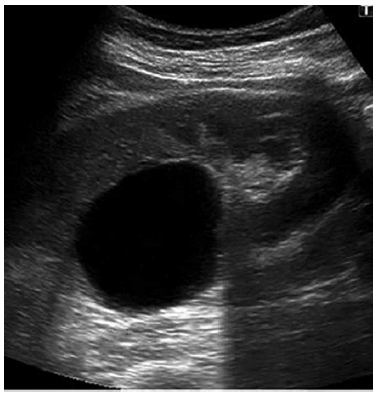

Paciente de 50 anos, sem comorbidades. Em exame de rotina, foi encontrada a imagem a seguir. Diante do achado da imagem, e com a opinião bem definida emitida pelo ultrassonografista no laudo, qual é a conduta mais adequada do nefro–urologista?